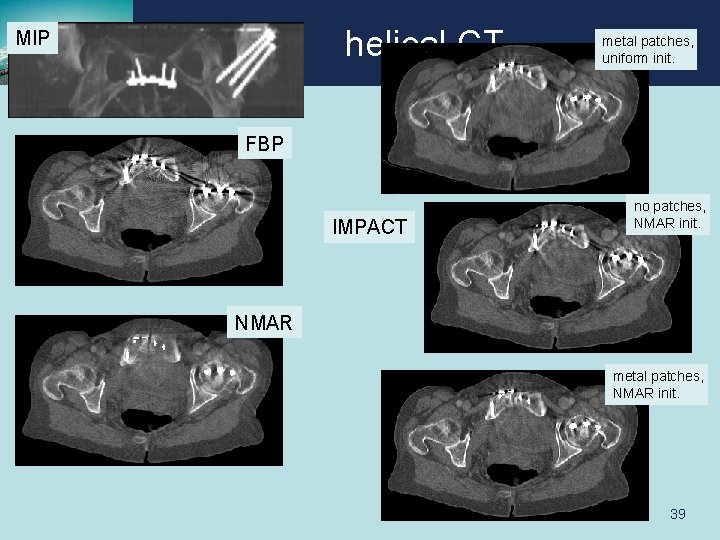

helical CT MIP metal patches, uniform init. FBP IMPACT no patches, NMAR init. NMAR metal patches, NMAR init. 5 iter x 116 subsets 38

helical CT MIP metal patches, uniform init. FBP IMPACT no patches, NMAR init. NMAR metal patches, NMAR init. 39